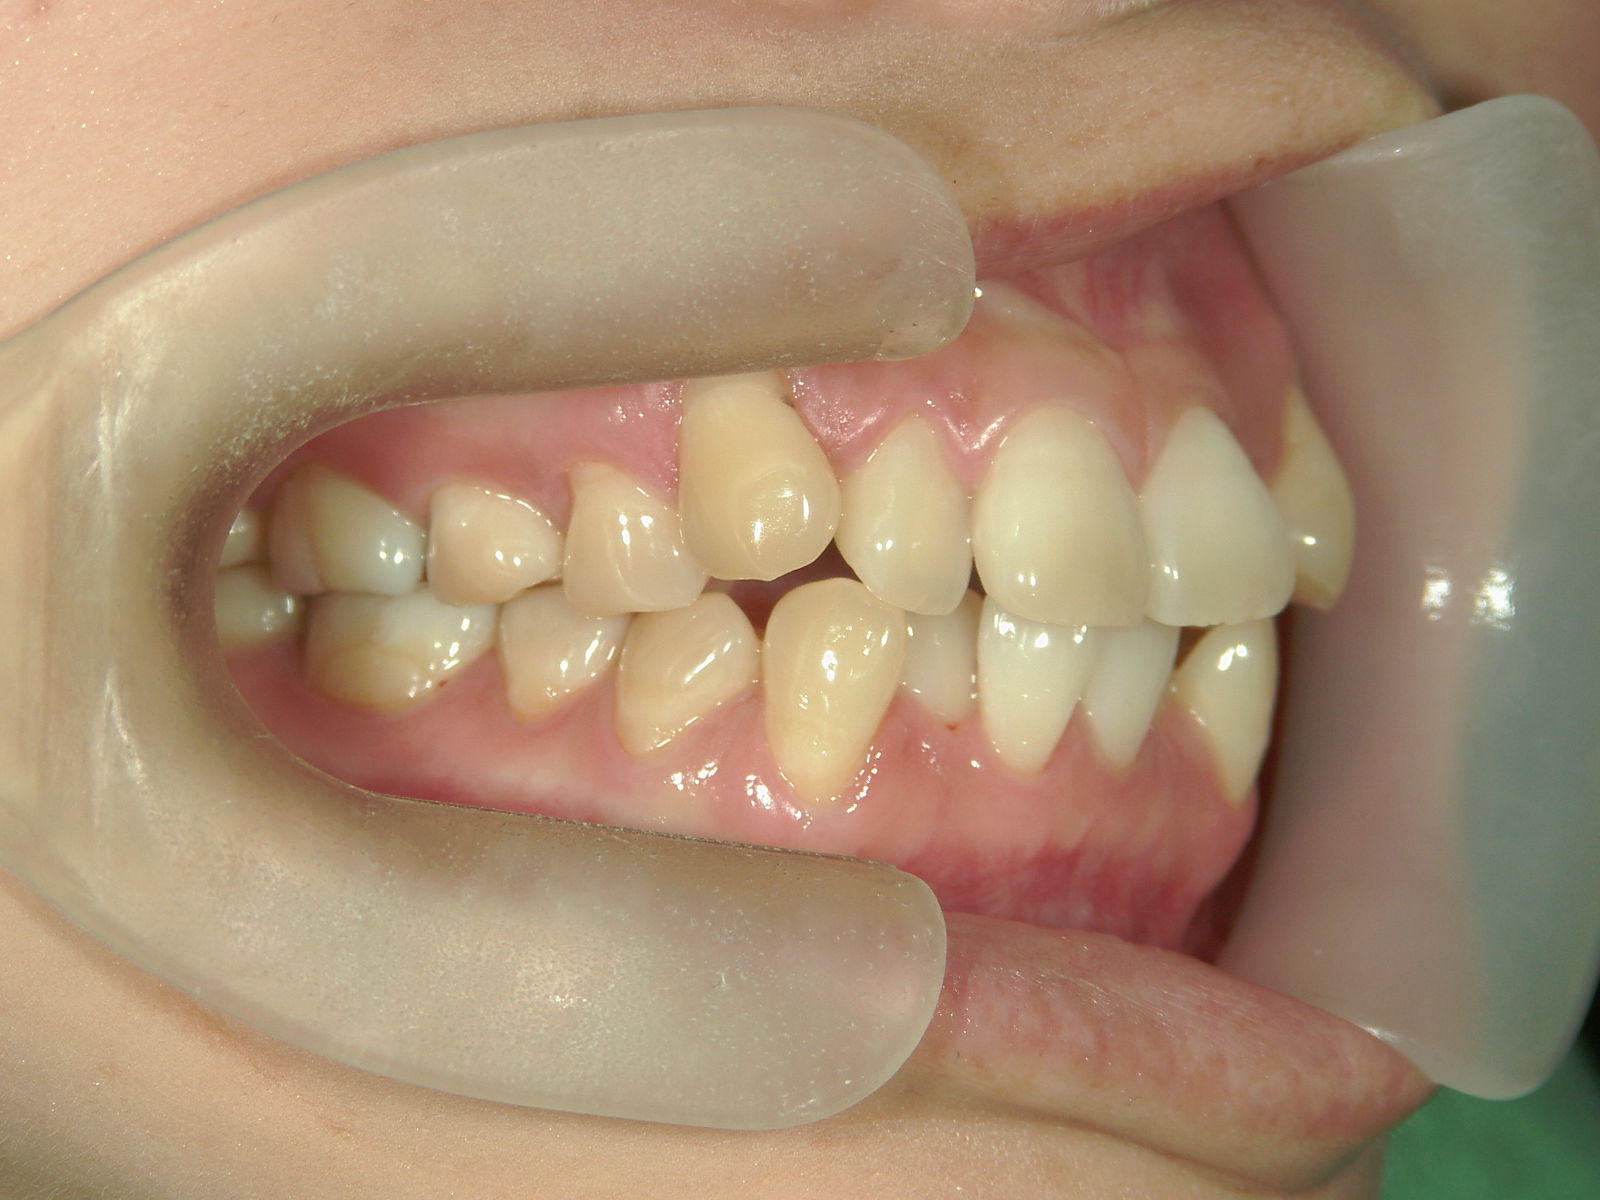

プチワイヤー矯正 症例(53)

主訴: 前歯の歯並びが気になる。

カテゴリー : ガタガタ(叢生)